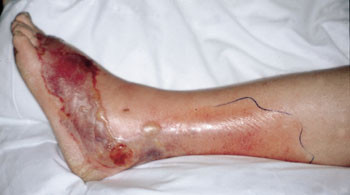

Nekrotiserende fasciitt kjennetegnes oftest ved et blekere rosa utslett med uskarpe grenser mot normal hud (fig 3, 4), til forskjell fra erysipelas, som vanligvis medfører et høyrødt utslett med skarp grense mot normal hud (fig 2). Sykdommen spres raskt i vevet selv under antibiotikabehandling. Utslettet bør kontrolleres ofte og grensene merkes med tusj og klokkeslett. Lokale, sterke smerter er karakteristisk. Feber og uforklarlige sterke smerter i en ekstremitet uten utslett bør gi mistanke om begynnende nekrotiserende fasciitt eller primær myositt. Disse sykdommene gir ofte sepsis med systemiske komplikasjoner, eventuelt som streptokokkbetinget toksisk sjokk-syndrom.

Kunnskapen om nekrotiserende fasciitt blant norske leger var mangelfull da denne sykdommen ble kjent for ca. ti år siden (14). Sykdommen var lite omtalt i lærebøker og diagnoselister (ICD-9/10), noe som har vanskeliggjort registrering og oppfølging. Ved Haukeland Sykehus har vi i perioden 1992 – 99 registrert 61 pasienter med nekrotiserende fasciitt, 15 overflyttet fra lokale sykehus, vesentlig Diakonissehjemmets Sykehus i Bergen. Inkludert i materialet var to pasienter med primær myositt. Dette gir en årlig insidens på mer enn tre per 100 000, noe som er meget høyt i verdenssammmenheng. I en større epidemiologisk studie i Ontario, Canada, ble det registrert 0,4 tilfeller per 100 000 innbyggere i 1995 (15). Til forskjell fra Ontario-studien, der mange pasienter var eldre med underliggende sykdom, var median alder på pasientene ved Haukeland Sykehus kun 49 år, og 74 % var tidligere friske. Små skader i huden før utviklingen av infeksjonstegn forelå hos 33 pasienter, noe som er rapportert i mange andre studier, og slike hudskader representerer en inngangsport for bakterier. Lesjonene var, som ved erysipelas, oftest lokalisert til ekstremitetene (underekstremitetene hos 27 og overekstremitetene hos 23), men det var også fem pasienter med nekrotiserende fasciitt i ansiktet, fem i genitalia og én med primærlesjon på thorax.